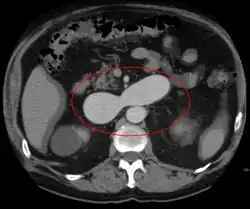

AVMs can occur in various parts of the body:

- brain (cerebral AV malformation)

- spleen[13]

- lung[14][15]

- kidney[16]

- spinal cord[17]

- liver[18]

- intercostal space[19]

- iris[20]

- spermatic cord[21]

- extremities – arm, shoulder, etc.